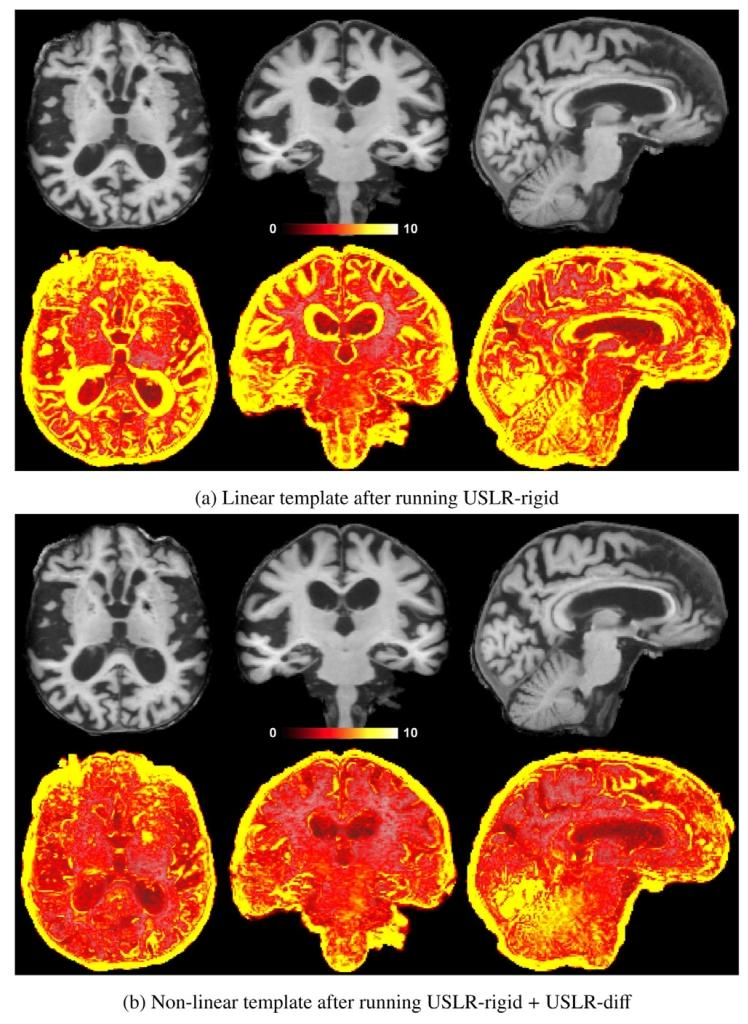

Fig. 4. Example of a template of an Alzheimer’s disease subject followed-up for atotal of 7.5 years with 𝐿 = 11 scans from a local cohort. On the top row, the meanT1w subject-specific template and on the bottom row, the standard deviation of theintensities between all the resampled and normalised timepoints. The larger variance inthe linear template leads to misleading intensity values, such as around the ventricles,where it looks like grey-matter tissue. The non-linear template is sharper and preventsartificial intensity values.

图4 一名阿尔茨海默病受试者的模板示例,该受试者来自本地队列,随访总时长为7.5年,共进行了𝐿=11次扫描。上行图像为受试者特异性T1加权平均模板,下行图像为所有重采样和标准化时间点之间的信号强度标准差。线性模板的较大方差会导致误导性的强度值,例如在脑室周围区域,其表现类似灰质组织。而非线性模板更清晰,可避免出现人工伪影强度值。